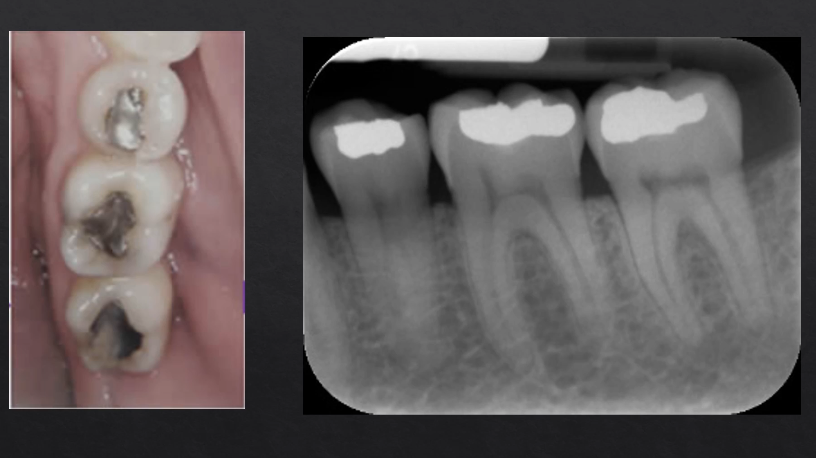

what can we determine from this radiograph?

the densest part of the tooth - enamel - appears most radiopaque as it absorbs/stops the most Xrays

dentine is more radiolucent

pulp is most radiolucent as its not calcified

silver/amalgam restorations absorb the most Xrays - most radiopaque